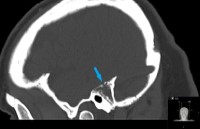

This is a 28 year old female who presents with complaint of right-sided hearing loss and sense of fullness within her right ear.

Her exam is consistent with conductive hearing loss in right ear.